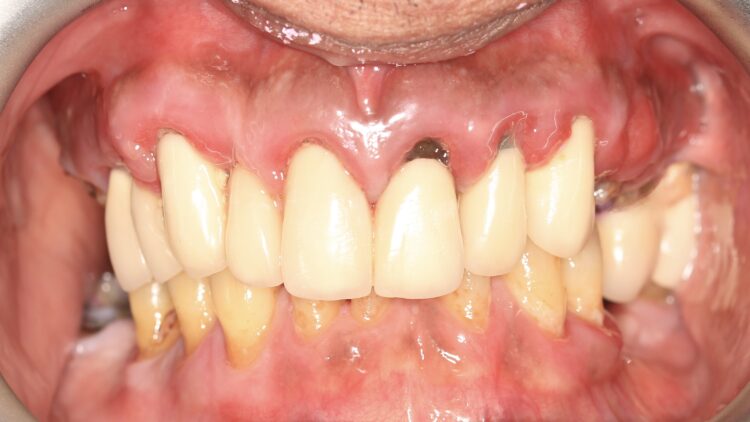

A 60-year-old male patient presented with major concerns about unsatisfactory smile appearance, limited masticatory function and pain while chewing. The patient was in good general health. The clinical and radiographic examination revealed failing ceramic restorations, rampant caries, non-restorable teeth, soft tissue inflammation, residual roots and missing teeth. Comprehensive digital records, including extraoral and intraoral clinical photographs, were collected as part of the initial assessment. The case was deemed suitable for full arch implant-retained restoration using advanced techniques.